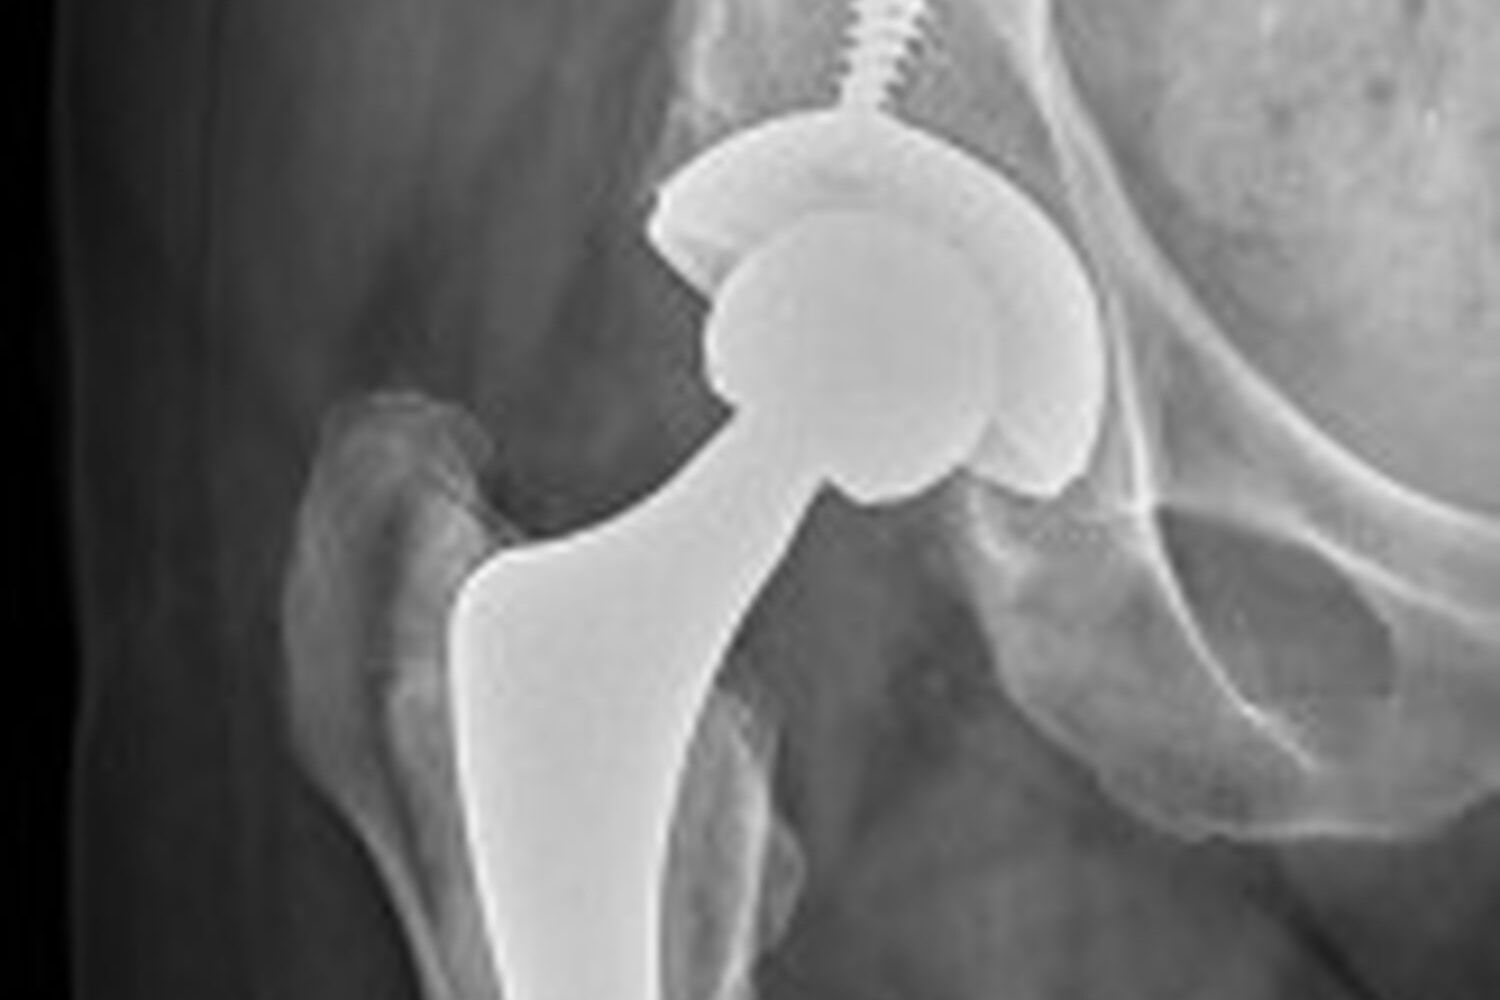

Hip

- Joint Replacement